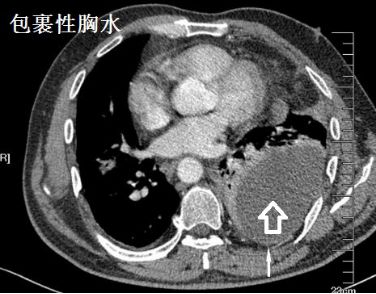

蜘蛛网胸水,也叫蜂窝状胸水,我发明的词汇,专业场合请用“包裹性胸水”!要不然查病历的把你这个月那点可怜的毛工资扣得连毛都没有!

蜘蛛网胸水(包裹性胸腔积液),在胸腔镜下是什么鬼样子的呢?

一大包胸水,看着是不是很好抽?嗯,轻松搞定!

为什么会酱紫?明明有胸水啊!明明确实有胸水,只不过......

且看胸腔镜:

胸腔里面这么多分隔,你能保证你的针在哪个小分隔里面?除非你有孙悟空的火眼金睛!